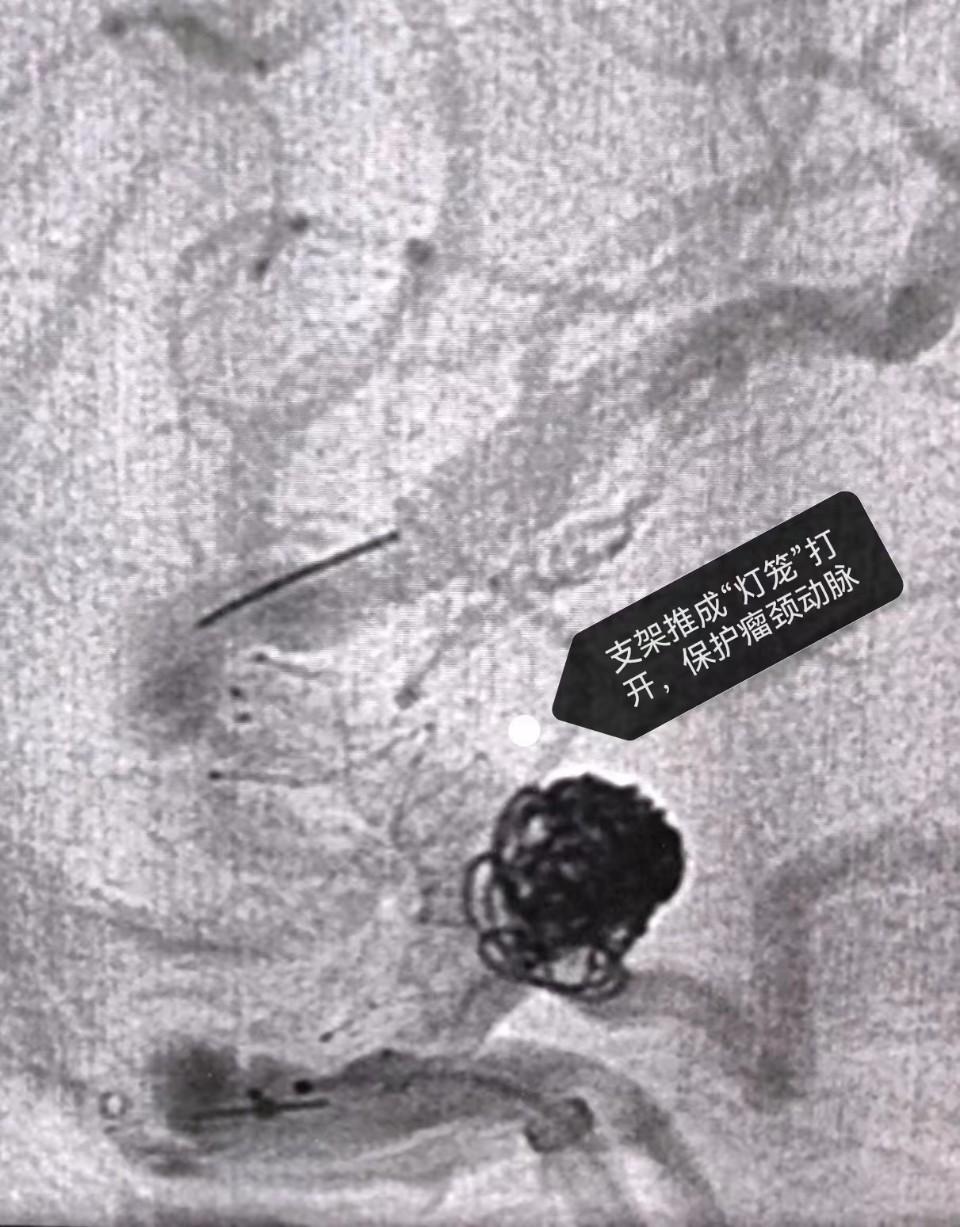

胜利油田中心医院脑科医院副院长宗强和神经外科介入亚专科带头人王瀚在仔细询问患者病史及阅片后,考虑患者右侧瘤体较大,破裂风险更高,决定先行右侧手术。但患者右侧颈内动脉末端伴重度狭窄,且瘤颈宽,需支架辅助,如果支架在血管狭窄处无法打开,将会造成血管的闭塞;另外,有一粗大的动脉从瘤体发出,栓塞动脉瘤的同时必须保证该血管的通畅,进一步增加了手术难度。神经外科团队经仔细讨论后,制定了缜密的手术方案,对动脉瘤破裂、支架打开不充分、后交通动脉的保护等做了详细的应急预案,最终手术顺利完成。朱女士术后第1天即可下地活动,术后第3天就顺利出院,据朱女士回忆,“感觉自己就是来美美地睡了一觉,根本没有做手术”。